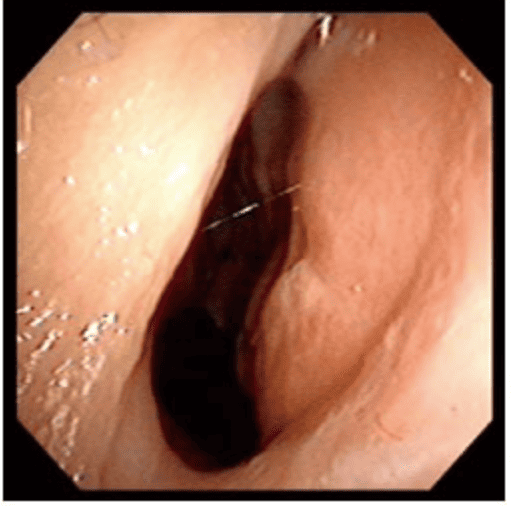

透過內視鏡檢查時,發現F先生右側尾端鼻中隔彎曲,幾乎貼近側壁,而且右側鼻阻力圖呈水平,代表F先生右側鼻空肌膚不能呼吸。鼻中隔軟骨扭曲變形、左上側軟骨凹陷萎縮,我們團隊先進行鼻部結構拆解及鼻中隔成形手術,再利用取下的鼻中隔軟骨進行重建,同時進行右側截骨術(Osteotomy),從根本矯正歪斜的鼻樑。

▲透過手術前後鼻阻力圖對照,術前右側鼻阻力線都接近水平線,表示呼吸阻力極大,術後鼻阻力線恢復正常曲線,接近兩邊對稱,表示呼吸恢復暢通,傷口也恢復良好。